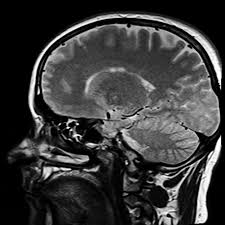

Der Tumor verdrängt oder zerstört also Hirngewebe und verursacht nicht nur lokal Ausfallerscheinungen sondern lässt auch den Druck im Schädelinneren ansteigen. Die Aphasie ist eine erworbene Sprachstörung. Von den vielen gutartigen benignen und oft heilbaren Tumoren.

Hierzu zählen zum Beispiel auch epileptiforme Anfälle oder Krampfanfälle. Von den vielen gutartigen benignen und oft heilbaren Tumoren. Das Problematische an Hirntumoren ist dass sie egal ob gut- oder bösartig in einer Körperregion wachsen die sich nicht nach außen ausdehnen kann. Wie äußert sich ein Hirntumor. Auch bei Krampfanfällen kann der Arzt manchmal auf den Ort des Hirntumors schließen. Hierzu zählen zum Beispiel auch epileptiforme Anfälle oder Krampfanfälle. Ein Hirntumor äußert sich oftmals auch durch psychische Veränderungen die auf keine bestimmte Ursache zurückzuführen sind.